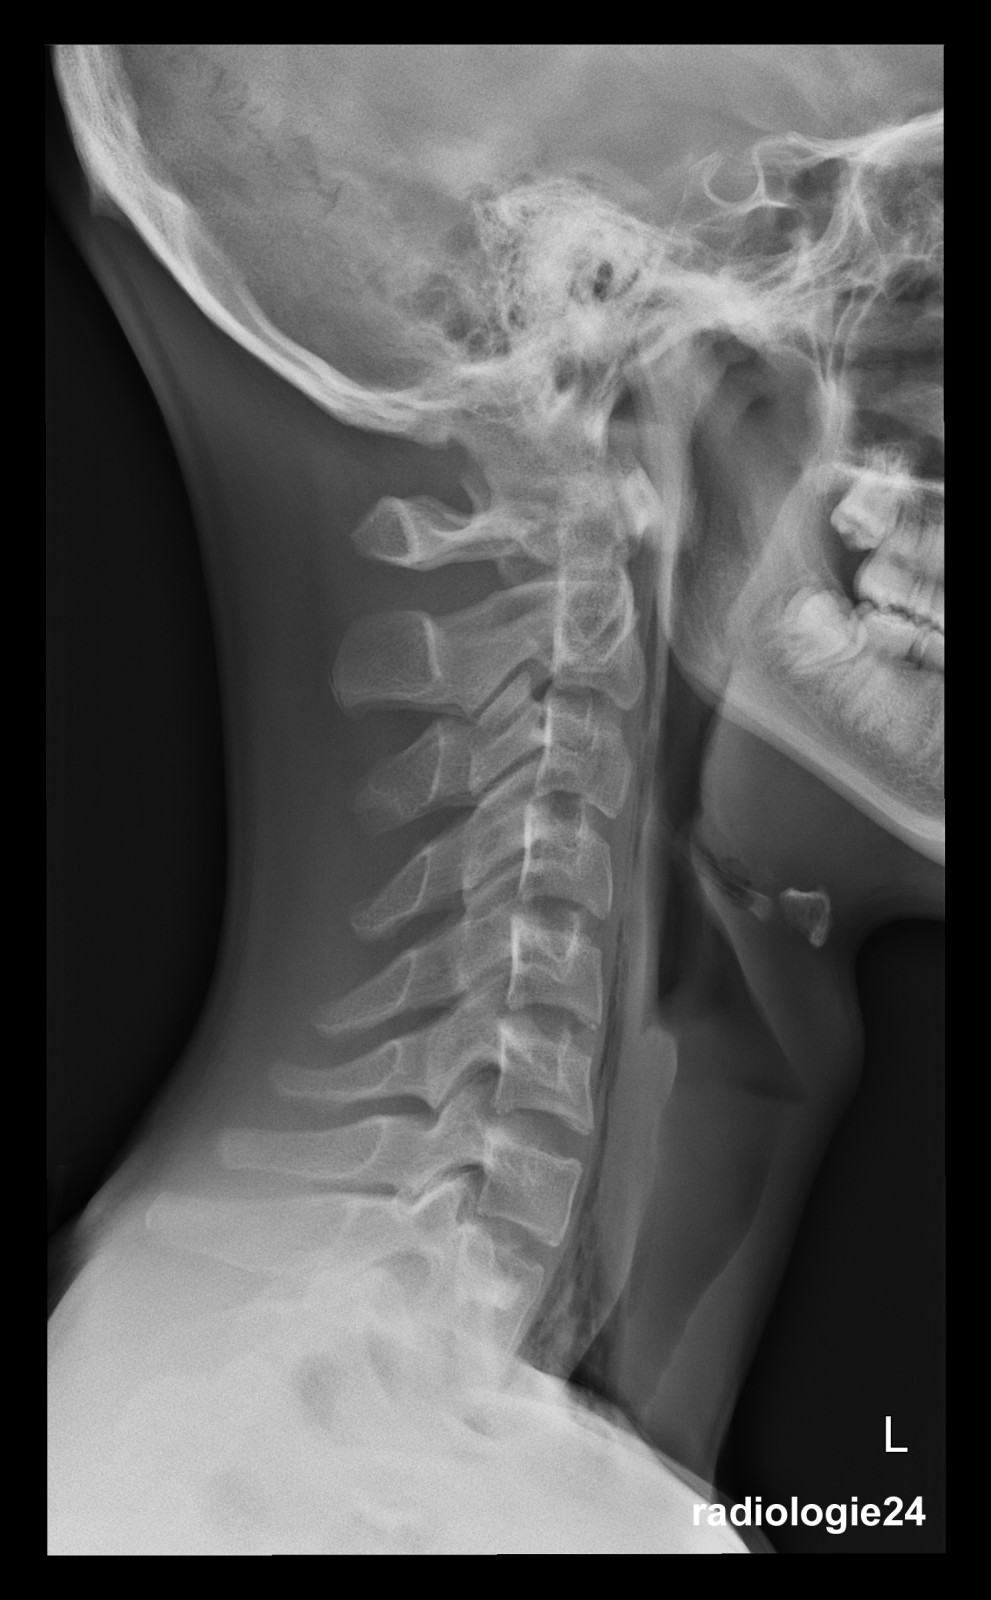

Röntgenfall des Monats Januar 2018 mit Auflösung

17 jähriger Patient Sturz auf den Rücken beim Crossbiken. Schmerzen HWS und Thorax. Fraktur, Pneumothorax, andere Pathologien? Weitere bildgebende Diagnostik? Welche? Warum?